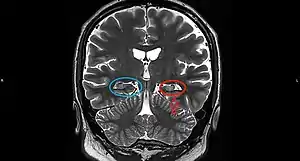

Hippocampal sclerosis (HS) or mesial temporal sclerosis (MTS) is a neuropathological condition with severe neuronal cell loss and gliosis in the hippocampus, specifically in the CA-1 (Cornu Ammonis area 1) and subiculum of the hippocampus. It was first described in 1880 by Wilhelm Sommer.[1] Hippocampal sclerosis is a frequent pathologic finding in community-based dementia. Hippocampal sclerosis can be detected with autopsy or MRI. In MRI, a decrease in signal is observed at T1 and an increase in signal at T2. Positron emission tomography is also used as an aid for diagnosis. In PET examination, glucose uptake is lower than in the normal part. The reason for this is that the sclerotic part works at a lower level than the normal part and needs less energy. Individuals with hippocampal sclerosis have similar initial symptoms and rates of dementia progression to those with Alzheimer's disease (AD) and therefore are frequently misclassified as having Alzheimer's Disease. But clinical and pathologic findings suggest that hippocampal sclerosis has characteristics of a progressive disorder although the underlying cause remains elusive.[2] A diagnosis of hippocampal sclerosis has a significant effect on the life of patients because of the notable mortality, morbidity and social impact related to epilepsy, as well as side effects associated with antiepileptic treatments.[3] Findings indicate that there is a strong genetic connection in the development of mesial temporal sclerosis.[4] Mesial temporal sclerosis used to be most commonly found as a single lesion in the brains of chronic epileptics who died a natural death which was estimated to be developed as a result of continued febrile convulsions.[5]

Mesial temporal sclerosis is a specific pattern of hippocampal neuron cell loss.[19][20] There are three specific patterns of cell loss. Cell loss might involve sectors CA1 and CA4, CA4 alone, or CA1 to CA4.[20] Associated hippocampal atrophy and gliosis is common.[19] MRI scan commonly displays increased T2 signal and hippocampal atrophy.[19] Mesial temporal sclerosis might occur with other temporal lobe abnormalities (dual pathology).[19] Mesial temporal sclerosis is the most common pathological abnormality in temporal lobe epilepsy.[19][20] It has been linked to abnormalities in TDP-43.[21]